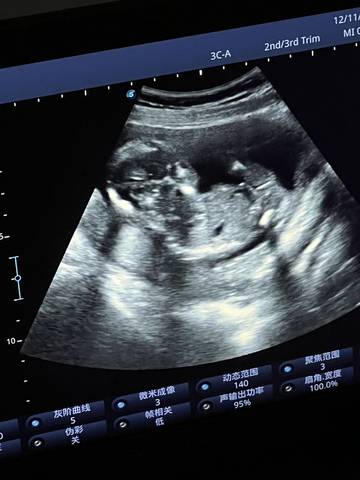

各位宝妈们,麻烦帮我看一下这是男孩还是女孩,好奇心满满????

journal_insert_pic_1678140510journal_insert_pic_1678140553

你好亲爱的,通过这个来判断男孩女孩是不太准确的哈。那么这个男孩女孩都是我们最爱的宝贝哈,我们要给他同等的关爱和呵护,也祝你可以如愿以偿,心想事成,祝你好运。

您好,看着这个图片有点感觉是个男孩子来的,不过建议你到时候有宝宝的图片的时候再发出来看一下

你好,根据你发的检查报告是看不出来宝宝的性别的,建议宝妈还是安心养胎,只要宝宝健健康康的就好

通过这些是看不出来的,而且也不准确,在怀孕期间的话你也不要想太多,我觉得只要宝宝发育好的话就可以,男孩女孩都一样的。